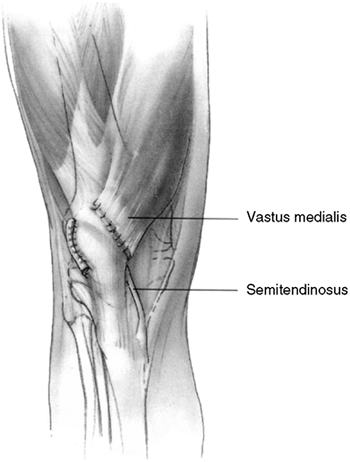

Figure 32.3 Patellofemoral biomechanics. A:

The Q angle relates the direction of pull of the quadriceps mechanism to that of the patellar tendon. These are the two most powerful forces exerted on the patella. Their vector sum is directed laterally. B: There are additional soft tissue forces applied to the patella. C: The laterally directed net vector is opposed by the patellofemoral articulation. If the groove is shallow, there is less potential resistance to horizontal translation than in knees with a deeper femoral groove. The dysplastic patellofemoral articulation results in less resistance to lateral translation, and therefore greater sheer forces on the articular surface. |